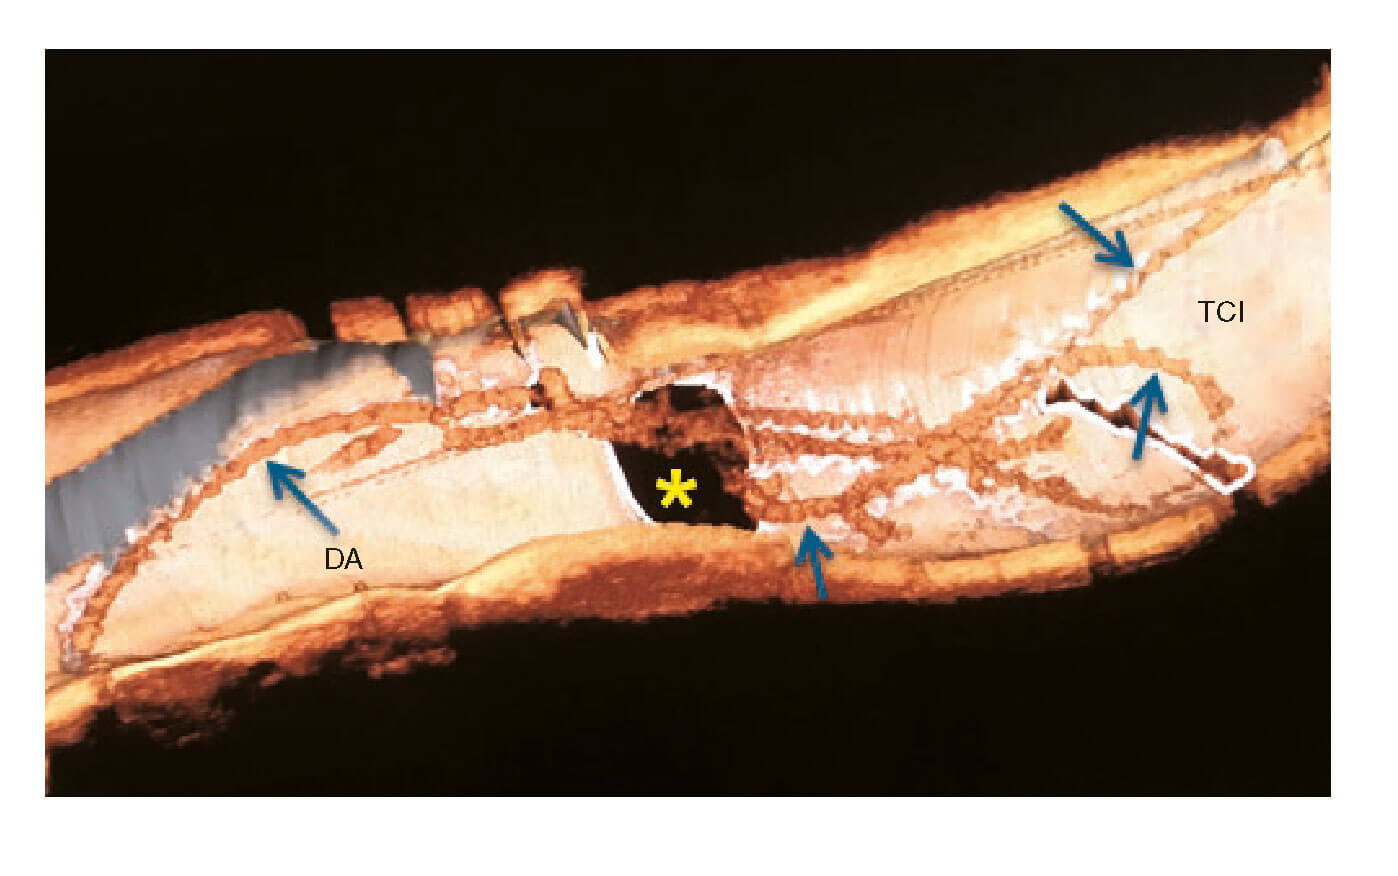

Después de implantar sin complicaciones un SFA en la DA media, se realizó una tomografía de coherencia óptica (OCT). La reconstrucción tridimensional llevada a cabo confirmó la presencia de restos de la guía rota (figura 2; flechas azules) saliendo de la Cx (figura 2; asterisco amarillo) y entrando en el tronco coronario izquierdo (TCI) y en la DA proximal y con material trombótico adherido y flotando libremente, tal y como revelan los cortes transversales (figura 3A y figura 3B; las flechas azules apuntan a los restos de la guía; la flecha amarilla, al material trombótico; ALM, área luminal mínima; vídeo 2 del material adicional). Se procedió a eliminar inmediatamente los filamentos deshilachados y a implantar un SFA en el TCI distal y en la DA proximal. La OCT de control confirmó el atrapamiento de la guía por los struts del stent contra la pared del vaso (figura 3C; flecha blanca: restos de la guía, resaltado en la caja remarcada en rojo; asteriscos rojos: struts del stent).

Figura 2